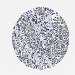

LIVER CANCER - Protein expressioni

A mouse-over function shows sample information and annotation data. Click on an image to view it in a full screen mode. Samples can be filtered based on level of antibody staining by selecting one or several of the following categories: high, medium, low and not detected. The assay and annotation is described here.

Note that samples used for immunohistochemistry by the Human Protein Atlas do not correspond to samples in the TCGA dataset.

Antibody stainingi

Antibody staining in the annotated cell types in the current human tissue is reported as not detected, low, medium, or high, based on conventional immunohistochemistry profiling in selected tissues. This score is based on the combination of the staining intensity and fraction of stained cells.

Each image is clickable and will lead to virtual microscopy that enables deeper exploration of all samples and also displays staining intensity scores, fraction scores and subcellular localization as well as patient and tissue information for each sample.

Antibody HPA019698

Staining

High

Medium

Low

Not detected

Intensity

Strong

Moderate

Weak

Negative

Quantity

>75%

75%-25%

<25%

None

Location

Nuclear

Cytoplasmic/membranous

Cytoplasmic/membranous,nuclear

Cholangiocarcinoma

Carcinoma, Hepatocellular, NOS